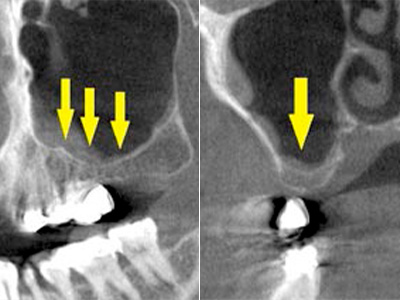

患者様は50代男性。インプラント治療前のレントゲン写真です。

右下顎大臼歯2本の抜歯後のレントゲン写真で、写真の黄色矢印は、歯の周囲の歯槽骨が大きく吸収されてしまっていました(黄色矢印)。 -

CTで見ると、骨吸収の様子が良く分かり、下顎骨の中を通る神経近くまで骨がありませんでした(黄色矢印)。